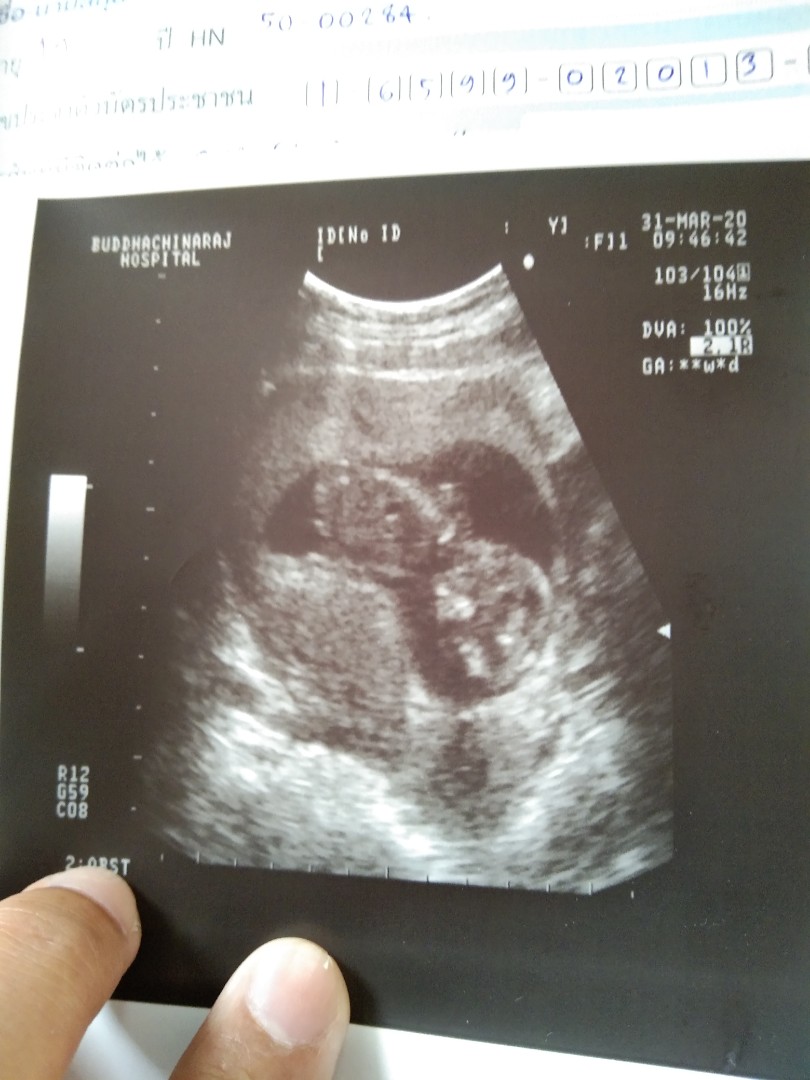

กำหนดคลอด 7 ตุลาคมจ้า ขนาดหมอไม่ได้วัดให้ค่ะเพราะวันนี้แม่มีเลือดออกช่องคลอดไปหาหมอก่อนกำหนดค่ะ นัด20เมษาค่ะ

กำหนดคลอด19ตุลาจ้า รูปนี้ตอน10Wจ้า ก่อนหน้านี้ไปซาวตอน5wยังไม่เจอตัวน้องค้ะพึ่งเจอตอน10w

ซาววันนี้จ้า 8/4/63 กำหนดคลอด17/10/63 จ้า ตอนป้าหมอซาวด์ให้ดิ้นดุ๊กดิ๊กใหญ่เลย 🤩

ซาวด์ตอน 11w+3 (20 มี.ค. 63)ค่ะ ดิ้นดุ๊กดิ๊กๆใหญ่เลยค่ะ กำหนดคลอด 6 ต.ค. 63 ค่ะ